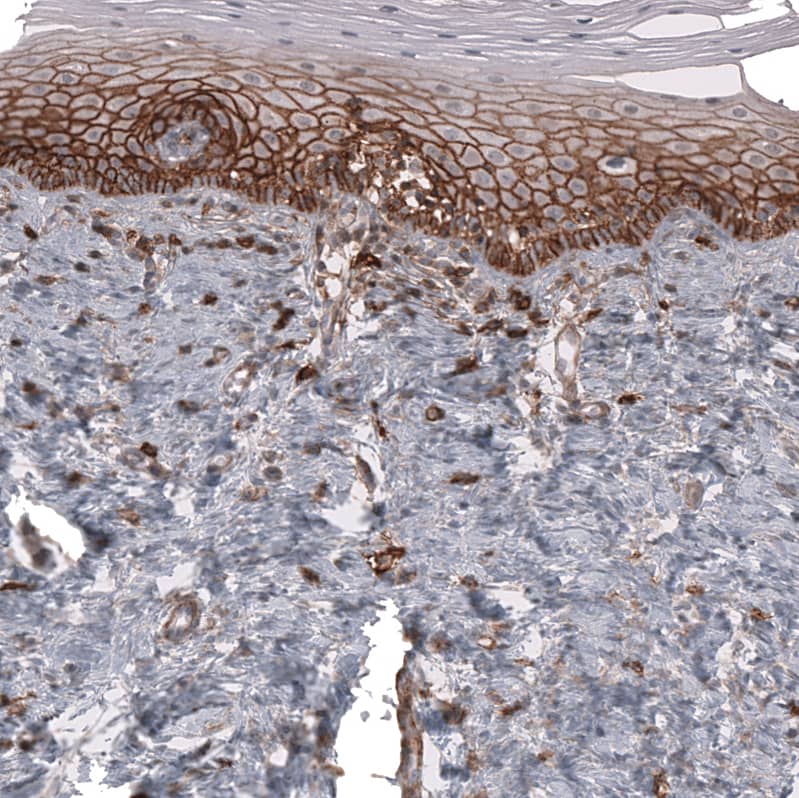

Staining of human uterine cervix shows moderate membranous positivity in squamous epithelial cells.